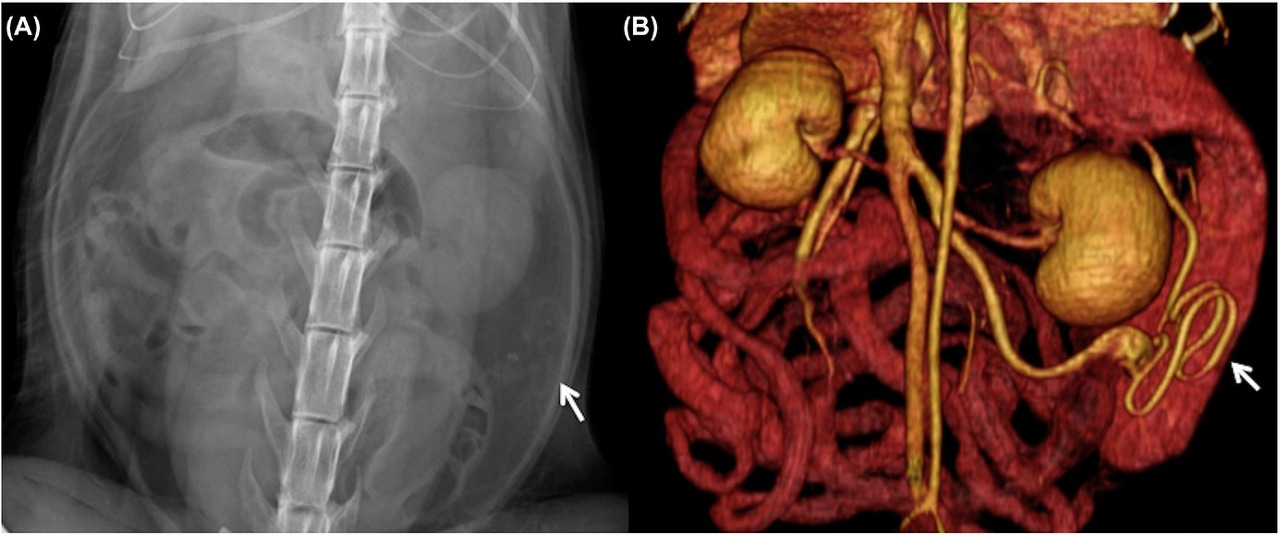

방사선 검사상의 소견은

이런 양상인데